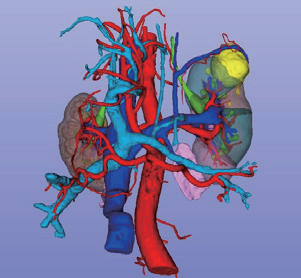

三维重建下的肾脏及其相邻脏器

三维重建泌尿系统动静脉预览

三维重建泌尿系统整体预览